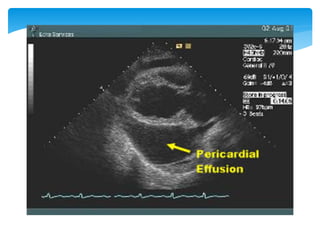

 Echocardiogram (diagnostic test of choice)

 Pericardial effusion

 Early diastolic collapse of the right ventricular free wall

 Late diastolic compression/collapse of the right atrium

 Swinging of the heart in its sac

 LV pseudohypertrophy

 CT scanning  Reveals compression of the coronary sinus an earlier marker for cardiac tamponade in 46% of patients.  Echocardiogram (diagnostic test of choice)  Pericardial effusion  Early diastolic collapse of the right ventricular free wall  Late diastolic compression/collapse of the right atrium  Swinging of the heart in its sac  LV pseudohypertrophy